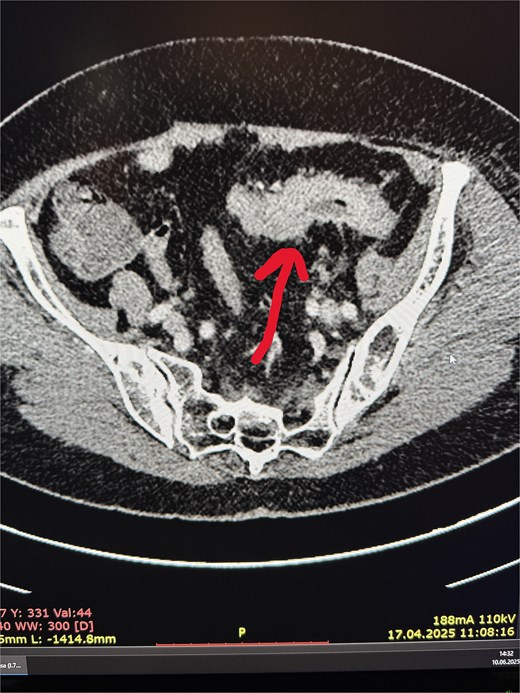

A 77-year-old female patient was admitted to the nephrology department due to diarrhea leading to dehydration and prerenal kidney failure. Due to accompanying abdominal pain, the diagnostic workup was expanded, and an abdominal computed tomography (CT) scan revealed:

irregular thickening of the sigmoid colon wall over a length of ~6 cm, with complete obstruction of the lumen in this segment (Fig. 1),

two cystic lesions on the periphery of the pancreatic tail, up to 7 mm in diameter, and one cystic lesion in the area of the pancreatic head and body (~10 mm),

numerous enlarged intraperitoneal and para-aortic lymph nodes (Fig. 2).